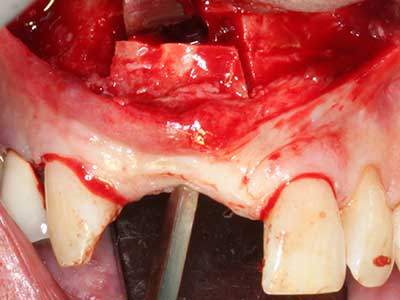

Костната тъкан е не само минерализирана структура, тя съдържа и съществено количество колагенови влакна. Това означава, че тя има не само добра компресивна сила, но и известна степен на гъвкавост, която може да се възприеме като предимство при извършване на костна аугментация. В класическата процедура по разширяване чрез костно разделяне, атрофиралият алвеоларен гребен е разделен надлъжно и внимателно разширен след достигане на подходящата остеотомна дълбочина (Фиг. 13-16), в идеалния случай без допълнително отстраняване на периостеума (Brugnami, Caiazzo et al. 2014, Stricker, Fleiner et al. 2014). Системите с винт и пластини с увеличаване на разстоянието при разширяване са доказали ефективността си при разделяне на двете костни ламели, оставайки под прага на фрактурите. В общи линии, оставащата ширина на костта от поне 3–4 mm е задължителна (Chiapasco, Zaniboni et al. 2006), за да се гарантира добра гъвкавост и достатъчно костно покритие за бъдещото поставяне на импланти. Ако е необходимо, вертикалната остеотомия на едната или двете страни може да подобри гъвкавостта. Комбинацията с допълнителни техники за аугментация, особено в букалната страна, е описана като алтернатива на класическата техника.